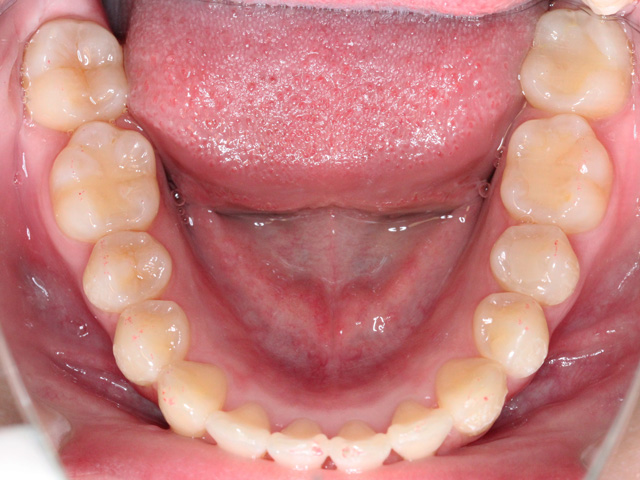

下顎の画像です。上と同じく前歯のスペースが不足しています。

右下の中切歯は「近心捻転(きんしんねんてん)」、左下の側切歯は「舌側転位」と呼ばれる状態になっています。